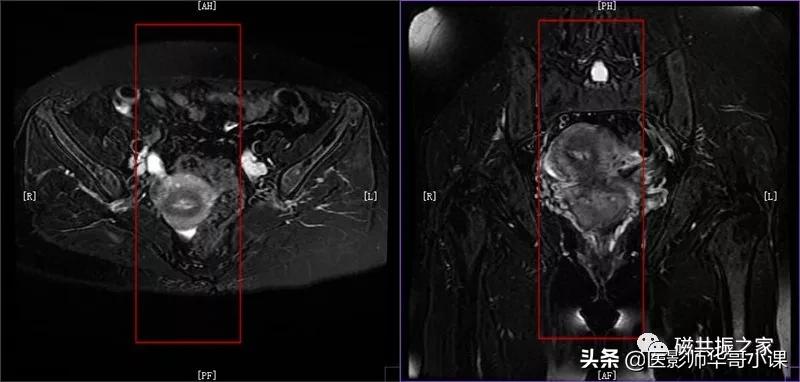

子宫MRI扫描前应先行1-2个大范围的 全盆腔 扫描序列,通常为大范围的T1WI和T2WI 压脂序列;在冠状位和矢状位上定位,按照常规的横轴位扫描即可。

行大范围扫描的目的:

1.了解盆腔内病变的大体情况。

2.观察盆腔内出血、转移、周围侵犯等情况。